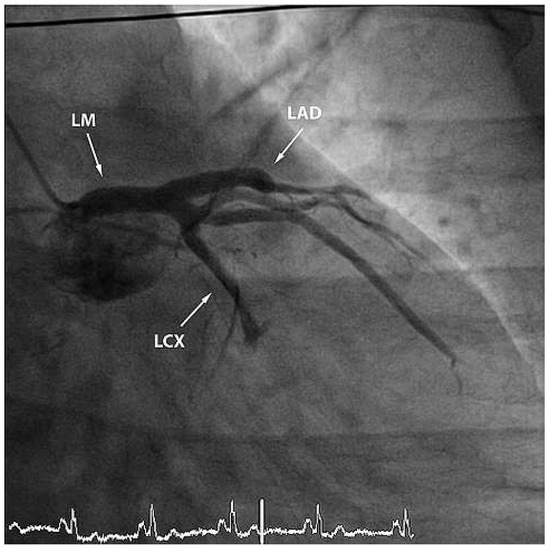

We report the case of a 47-year old man who presented with severe cardiogenic shock and signs of ST-elevation myocardial infarction. Urgent coronary angiography showed thrombotic occlusion of the mid left anterior descending artery (LAD) and the circumflex artery, as well as a [...] Read more.

We report the case of a 47-year old man who presented with severe cardiogenic shock and signs of ST-elevation myocardial infarction. Urgent coronary angiography showed thrombotic occlusion of the mid left anterior descending artery (LAD) and the circumflex artery, as well as a subtotal thrombotic occlusion of the right coronary artery without signs of relevant atherosclerotic coronary disease. The patient was treated with thrombus aspiration in all coronary vessels and PTCA of the LAD with good result. Despite thorough investigation of major nonatherosclerotic causes of myocardial infarction, which are further discussed in our case report, the case remains unsolved. Until today the patient is free of symptoms under long-term dual antiplatelet-inhibitor therapy. Full article